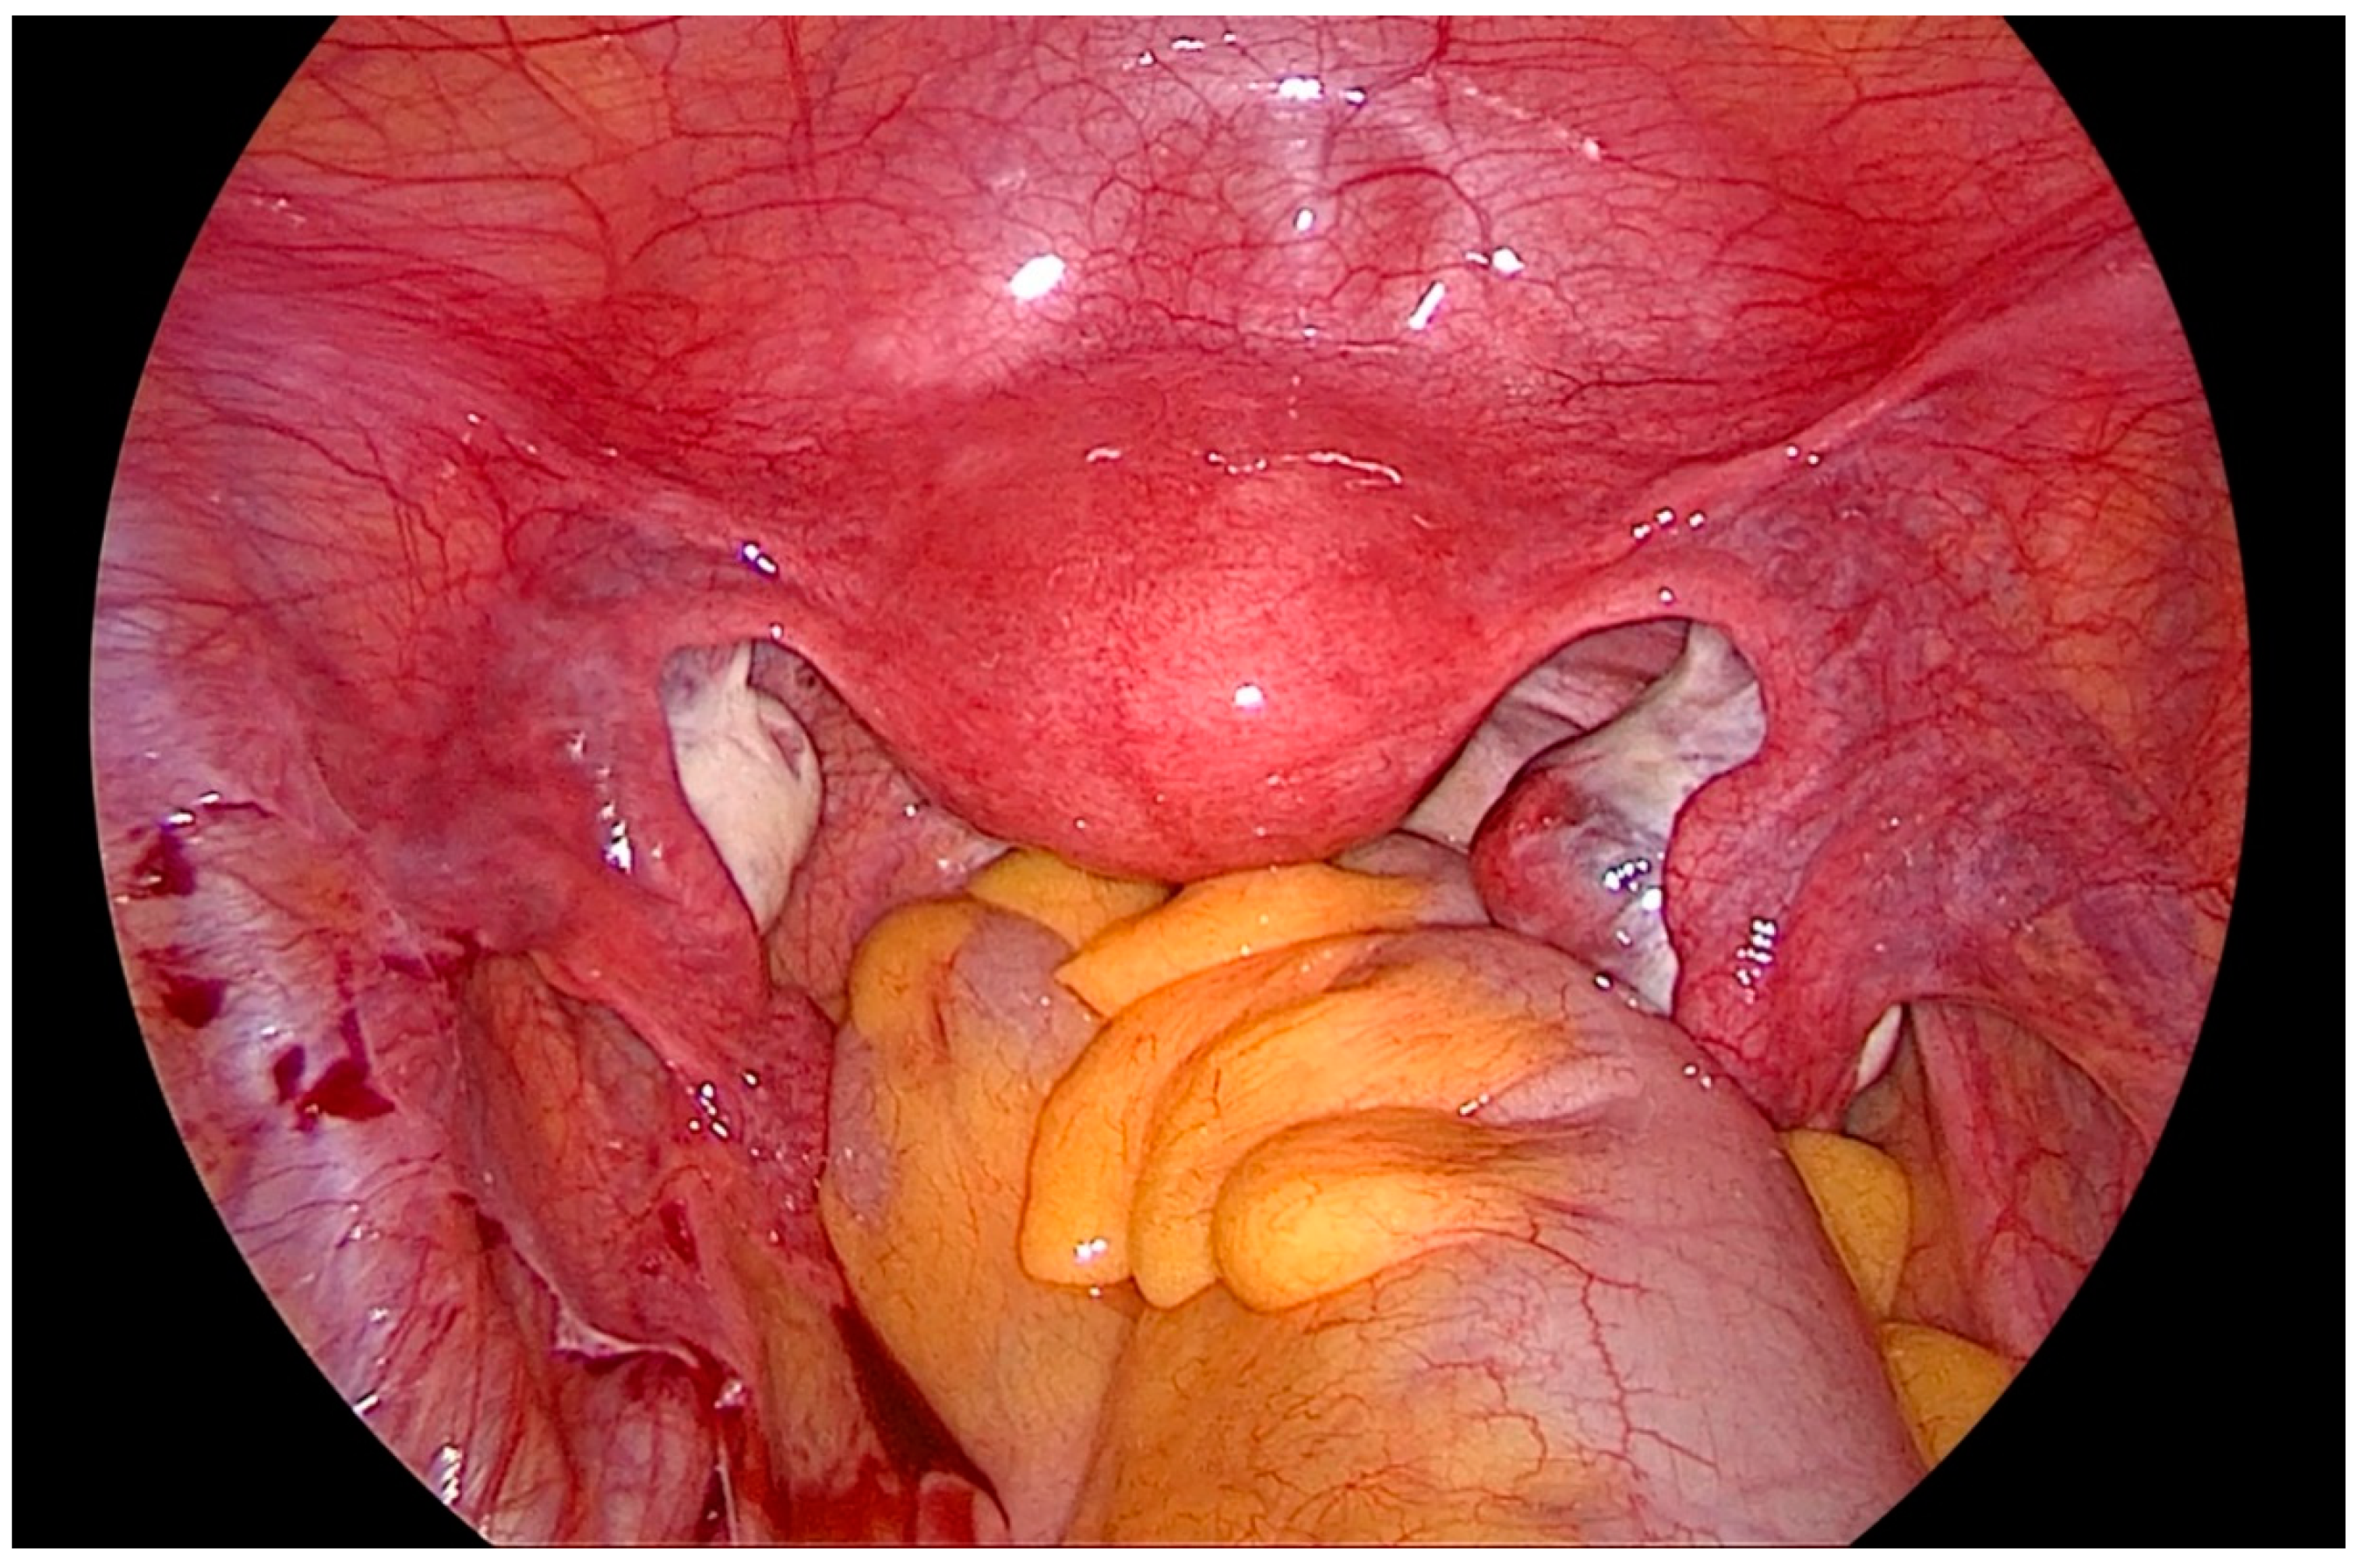

Figure 1.

Laparoscopic view of the pelvis, depicting the ovaries hampering vision and access to the lateral pelvic wall.